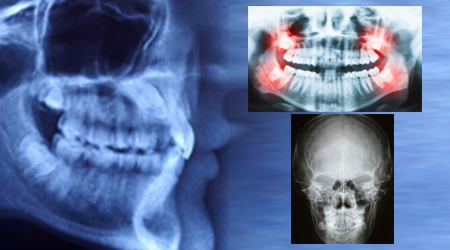

root-canal-treatment-in-gurgaon

root-canal-cost-in-gurgaon

RVG (Small X-Ray) 200 5

OPG (Full Mouth X-Ray) 500 10

CT Scan 5000 80